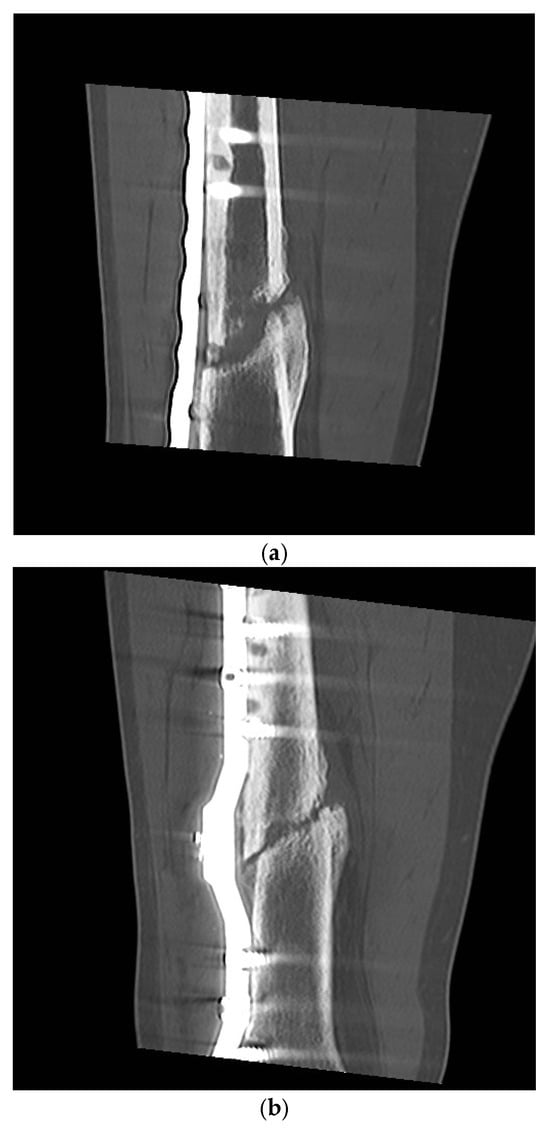

Plate and K-Wire Show Advantages to Nailing for Distal Diametaphyseal Radius Fracture in Children: A Retrospective, Two-Center Study

by Frederik Weil, Lucas Fabarius, Luisa Weil, Paul A. Grützner, Michael Boettcher, Christel Weiß and Stefan Studier-Fischer

J. Clin. Med. 2025, 14(13), 4626; https://doi.org/10.3390/jcm14134626 - 30 Jun 2025

Background/Objectives: Distal forearm fractures are the most common fractures in children. Three surgical techniques are most commonly used at the level of the radial diametaphysis on the distal forearm in children: K-wire, ascending ESIN (elastic stable intramedullary nail) or plate osteosynthesis. The [...] Read more.

Background/Objectives: Distal forearm fractures are the most common fractures in children. Three surgical techniques are most commonly used at the level of the radial diametaphysis on the distal forearm in children: K-wire, ascending ESIN (elastic stable intramedullary nail) or plate osteosynthesis. The aim of this study was to compare these procedures in children with distal diametaphyseal radius fractures regarding operative and functional outcome. Methods: A retrospective study was conducted in two level 1 trauma centers. Children and adolescents aged 2 to 15 years were included. The study period was from January 2010 to December 2022. The hospital information system was used to record patient age, gender, height, weight, fracture location, degree of angular deformity postoperatively, surgical procedure and postoperative complications, which were described in the medical records of the hospital information system. Complications graded by modified Clavien–Dindo–Sink served as the primary outcome. Reduction accuracy, operative and fluoroscopy times, immobilization length and postoperative motion were the secondary endpoints. Results: A total of 213 children were included in the study. K-wire osteosynthesis was performed in 25%, nailing in 19% and volar plate osteosynthesis in 55%. All ESIN were inserted in ascending technique. Complications occurred in 22% of patients and did not differ overall between techniques (p = 0.20). Severe complications were significantly more frequent after ESIN (20%) than after K-wires (7%) or plates (4%) (p = 0.04). Plate fixation achieved the most accurate alignment (≤5° angular deformity in 93% vs. 57% K-wires and 61% ESIN; p < 0.0001) and the fewest late motion restrictions (p = 0.02). K-wire surgery was fastest technique and required the least fluoroscopy, but necessitated the longest postoperative cast. Conclusions: Volar plating combines reliable anatomical reduction with a low rate of major complications and early mobilization, supporting its use in older children whose remodeling potential is limited. K-wires are a swift, minimally invasive option for younger patients, albeit with less precise reduction and prolonged immobilization. Conventional ESIN showed the highest burden of severe complications. Full article